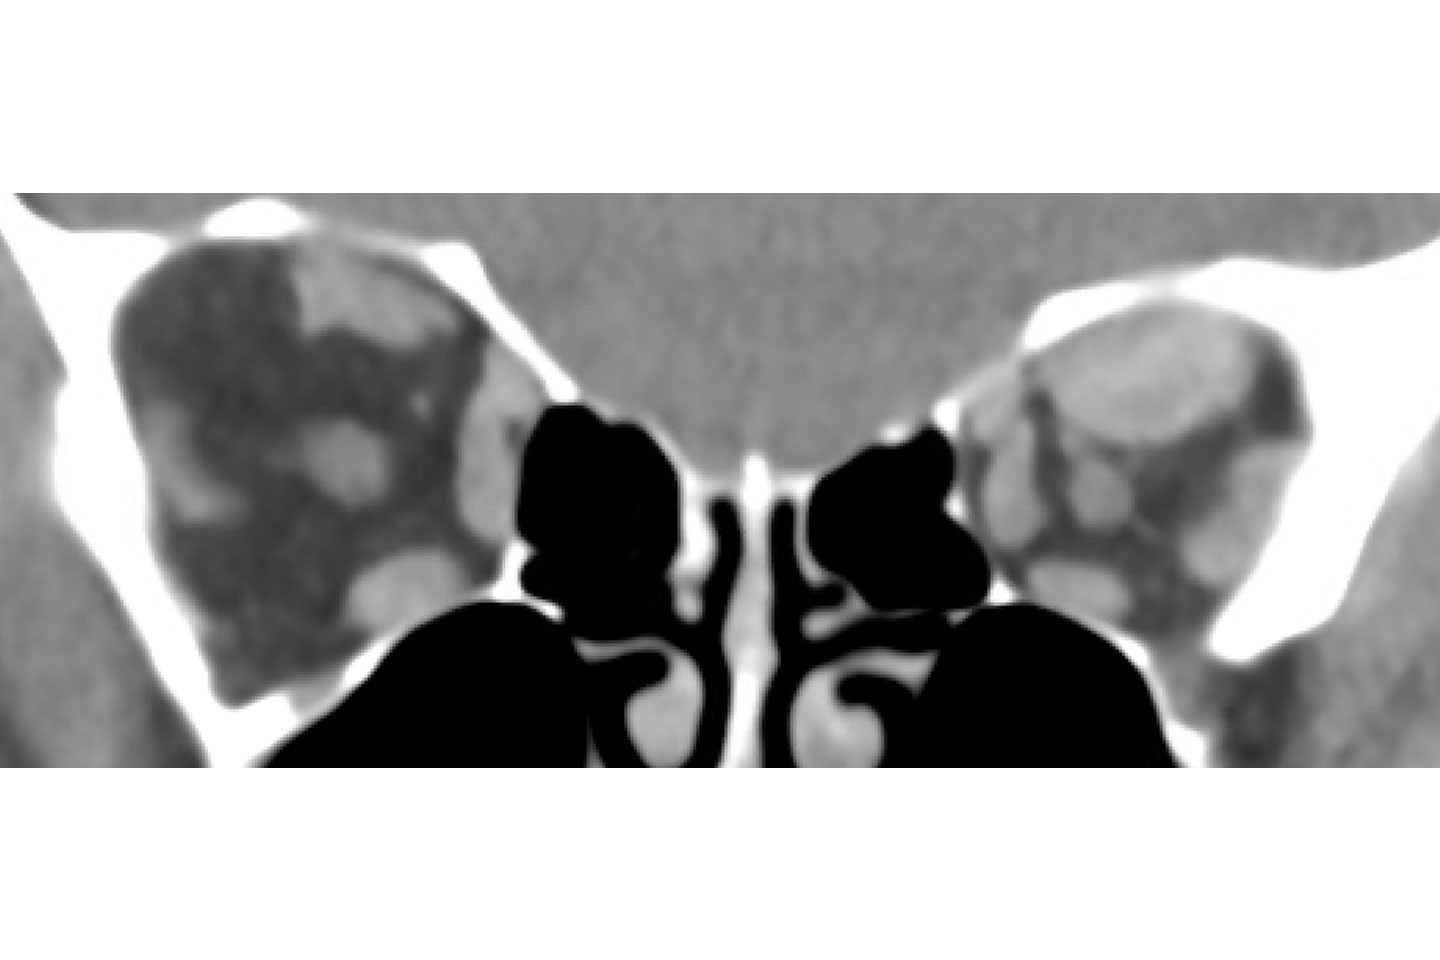

Coronal preoperative orbital imaging showing crowding of left orbital contents. Source: NYU Langone Health